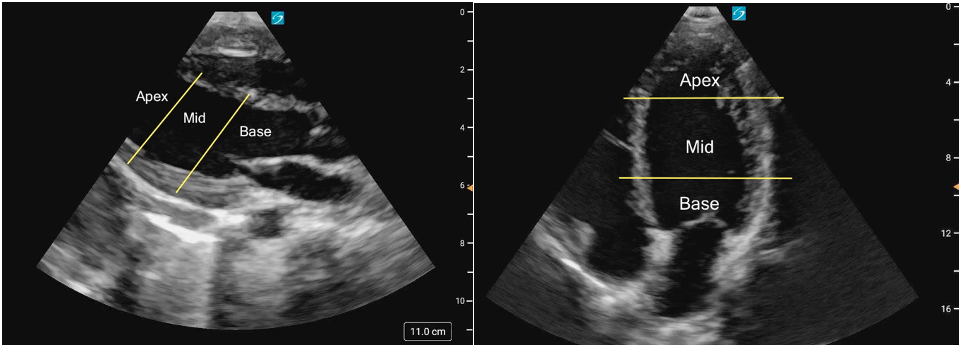

In A4C view, you can assess LV wall motion at the basal, mid, and apical levels of the inferoseptal and anterolateral walls (figure 19). This view is also useful for visual estimation of overall contractility and evaluation of the LV’s size and shape throughout systole and diastole.

Figure 19: Apical 4 Chamber view in cardiology convention with the labeled left ventricular walls